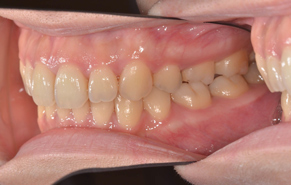

上下前歯のガタガタの症例です。ガタガタしている所は歯ブラシがとどかないので、茶色く着色しています。重なっている所は虫歯になっていることが、ほとんどです。

ガタガタの量が多く、物理的に顎の骨に入りきらないため、上下左右の前から4番目の歯(第一小臼歯)を抜いて、治療しました。抜かずに治療した場合、歯列の円周が広がり口元が突出してしまうため、抜歯をご選択されました。矯正後は歯磨きもし易く、歯の色も一緒にきれいになっています。